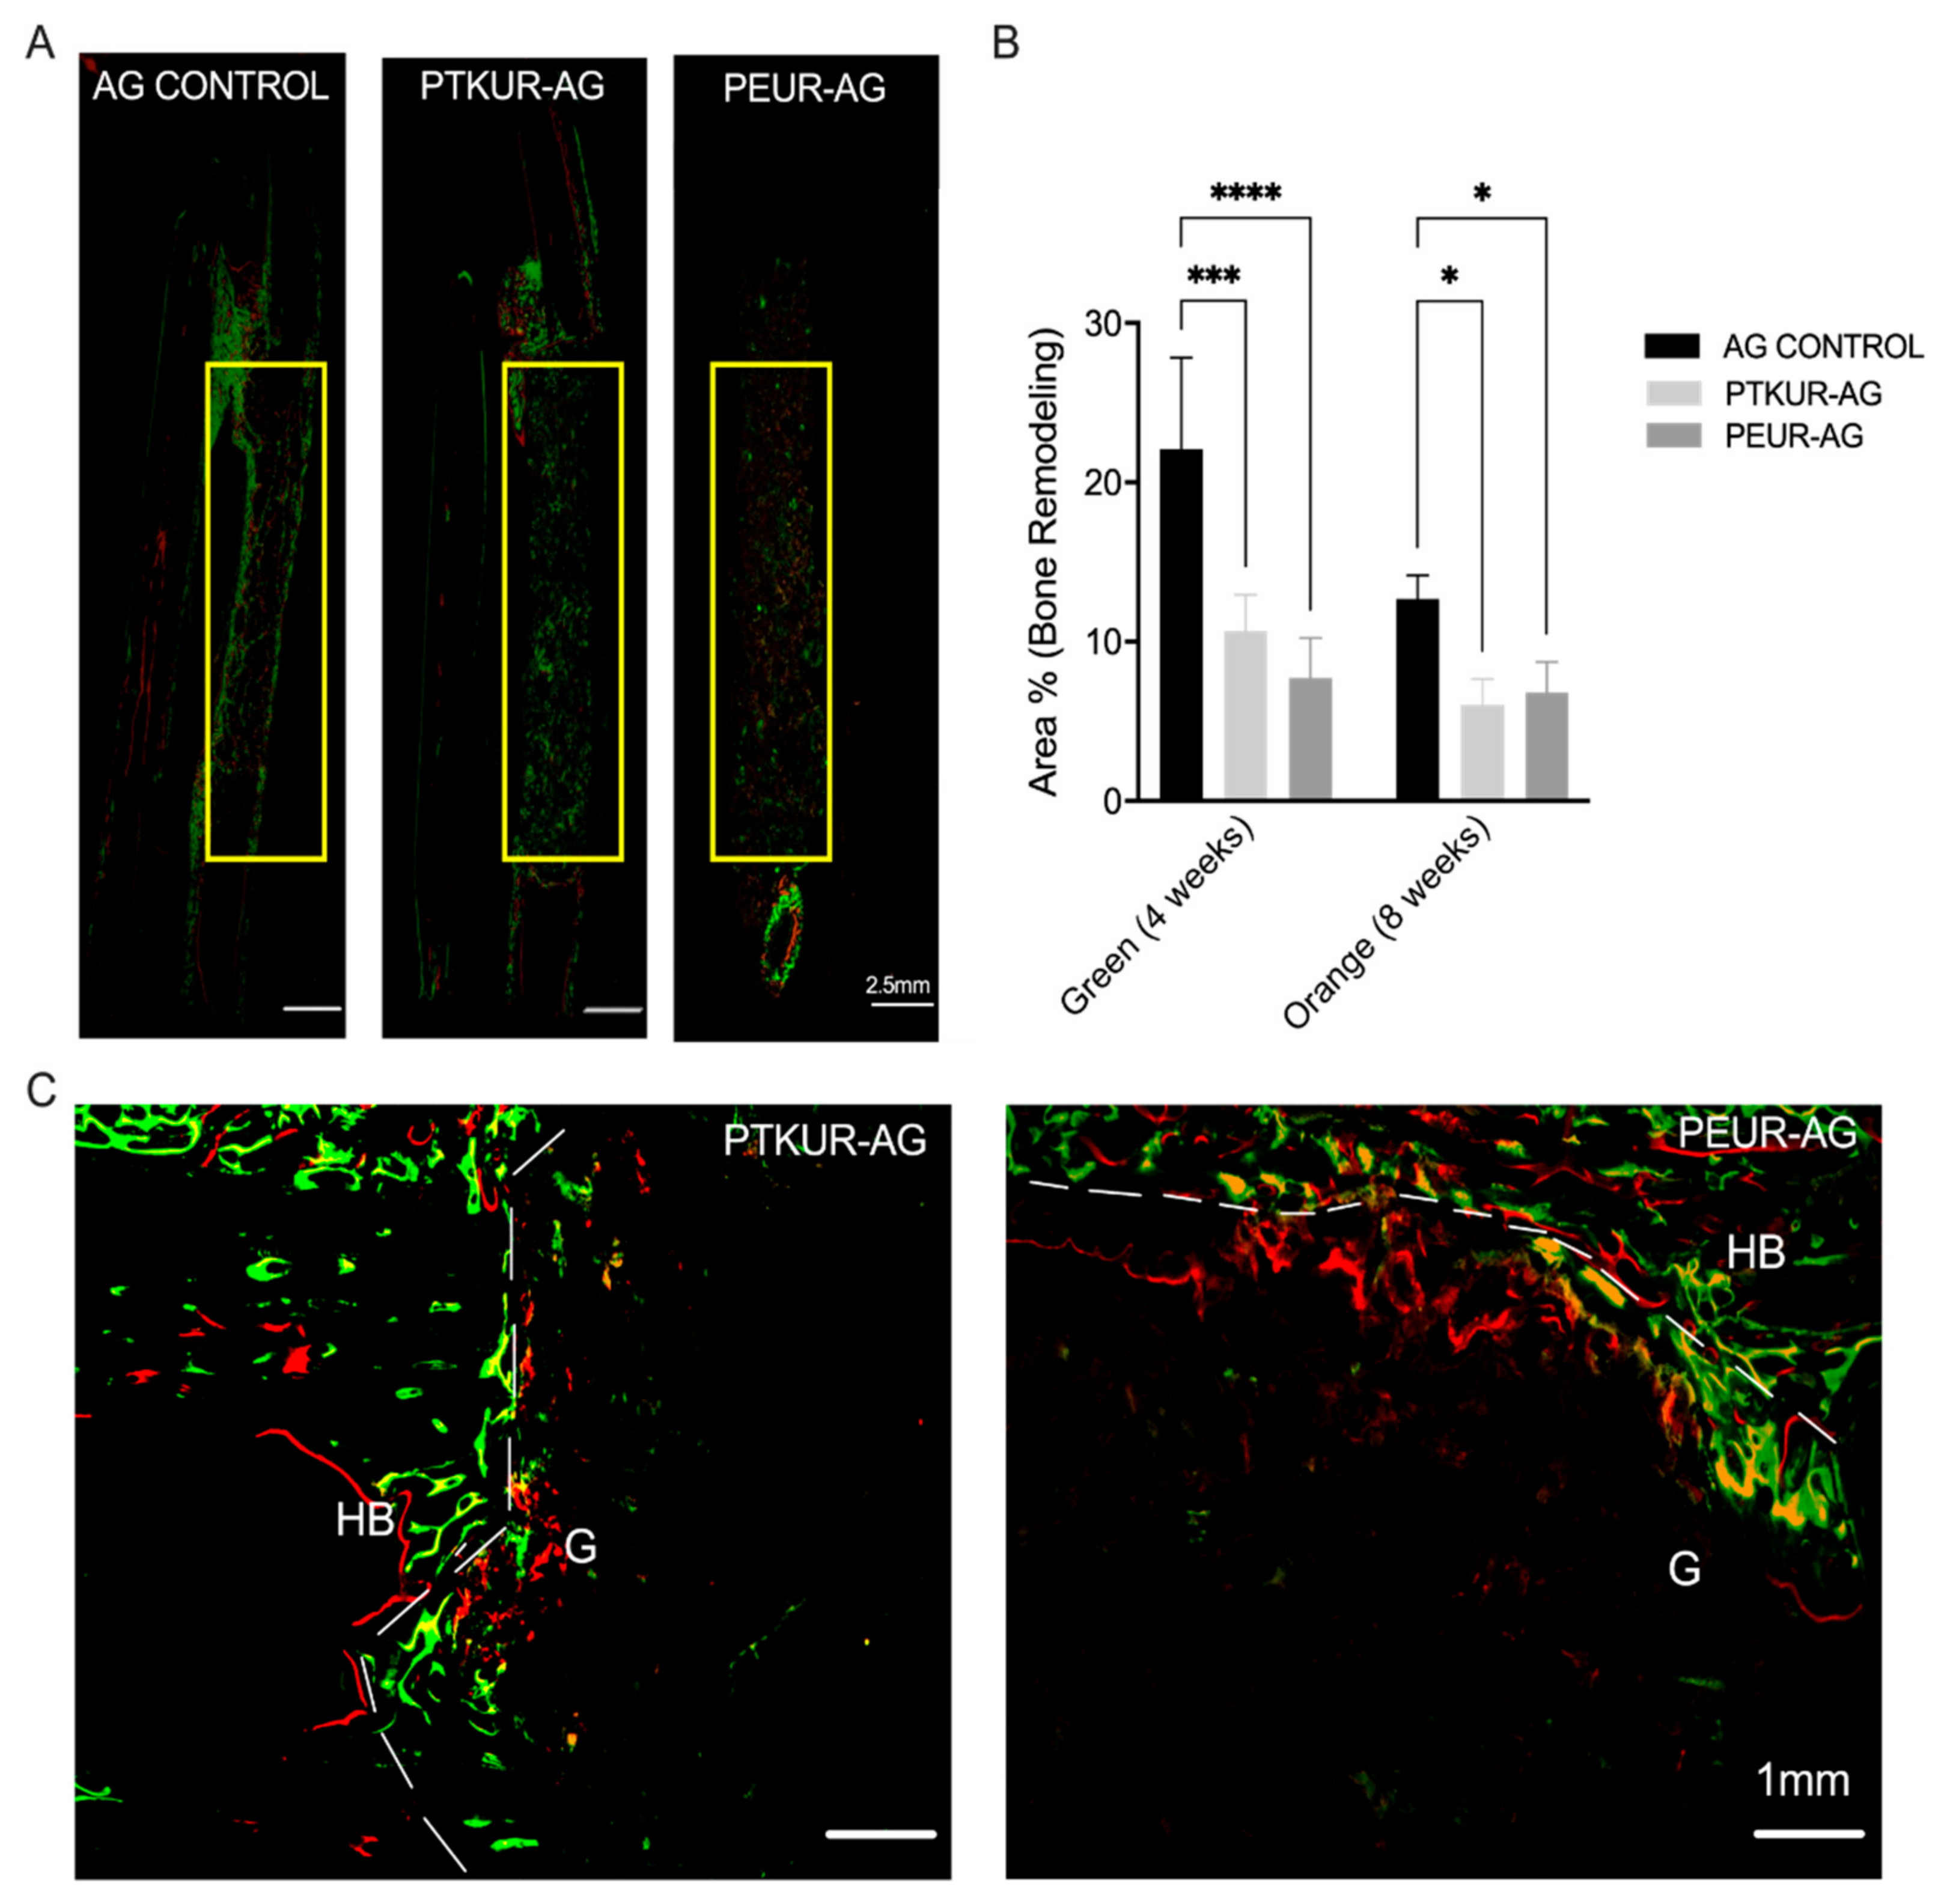

3.3. PTKUR and PEUR Graft Remodeling